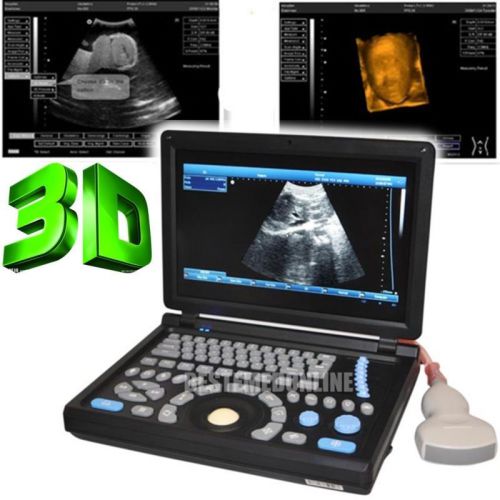

3D PC Platform Full Digital Laptop Ultrasound Scanner+ Convex &Linear BEST CHOIC

HOT HOT HOT! Digital Ultrasound Scanner 4-frequency Convex +Linear probes +3D

3D Digital Ultrasound Scanner +Convex TV 2 probes Optional 2 probes+3 years warr

ONLY 1-MONTH SALE!!! Digital Laptop Ultrasound Scanner Diagnostic + Linear 3D

NEW Full Digital TFT LCD Ultrasound Scanner High-resolution (built-in 3D) CONVEX

FULL DIGITAL Portable Ultrasound Scanner 3 probes "Convex,Linear,TV" +3D GOOD+++

3D Full-digital Ultrasound scanner machine with 3.5MHz R60 convex +2 USB Ports

Hot 3D Full-digital Ultrasound scanner machine W CONVEX +2 connectors+2USB ports

3D 10.1" Full Digital Laptop Ultrasound Scanner Machine +Micro-convex Probe CE

in 3D Full Digital Laptop Ultrasound Scanner (PC) with convex probe Free Ship

NEW 10.4" 3D PC platform Full Digital Laptop Ultrasound Scanner+ 3.5Convex Probe

+Aluminum box Full Digital 3D PC LAPTOP Ultrasound Scanner vaginal NEW